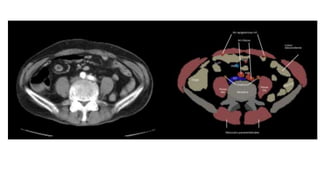

Asas dilatadas, colapsadas

o de calibre normal

Engrosamiento con

hipocaptacion de la pared

Ingurgitacion de vasos

mesentéricos

Obstrucción en asa cerrada

Colapso intestinal

Gas en sistema portal o

neumoperitoneo